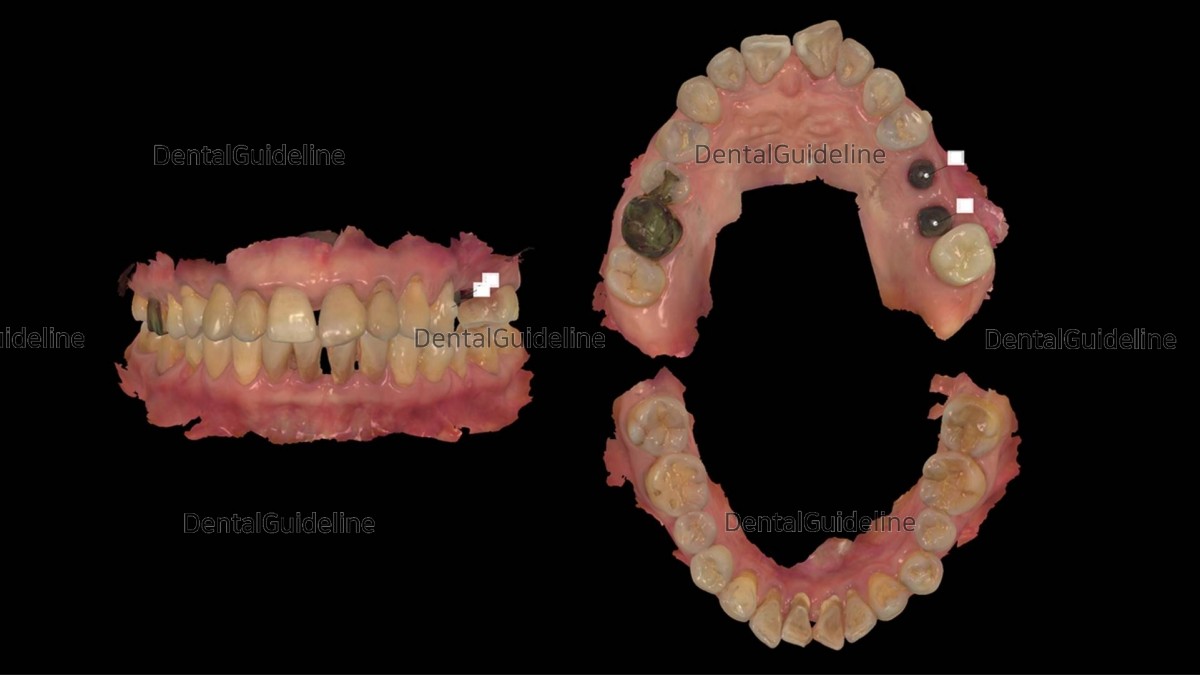

8. Gingival tissue punching was performed to expose fixtures. The 2nd molar showed unexpected mesial movement during the osseointegration period of the implant.

9. Intra-oral scanning was done to fabricate a tooth-positioning appliance for the 2nd molar distalization.